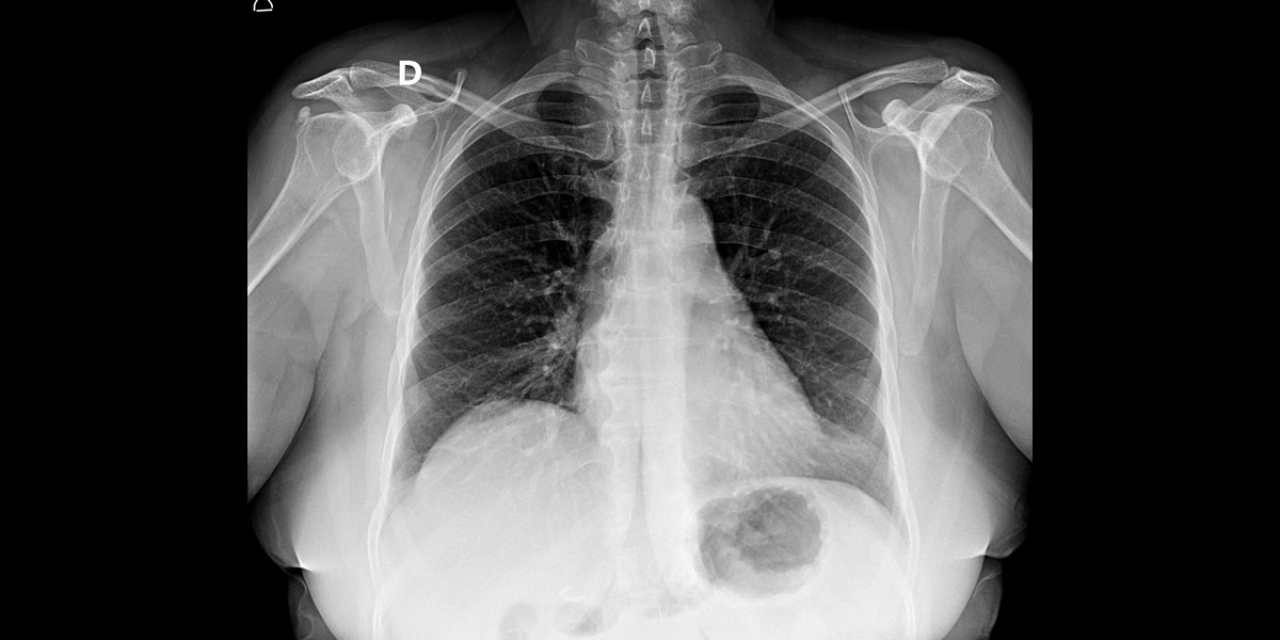

A Prefeitura de Bebedouro, através da Secretaria Municipal de Saúde (SMS), avança na modernização do serviço de diagnóstico por imagem, com a transição do sistema analógico para o digital.

Com a implantação do novo sistema, os exames e laudos passam a ser disponibilizados por meio de links seguros, facilitando o acesso rápido às informações. Além disso, todo o material ficará integrado ao prontuário eletrônico, disponível em toda a rede municipal de saúde, promovendo a continuidade do cuidado, maior precisão diagnóstica e melhor acompanhamento dos pacientes.